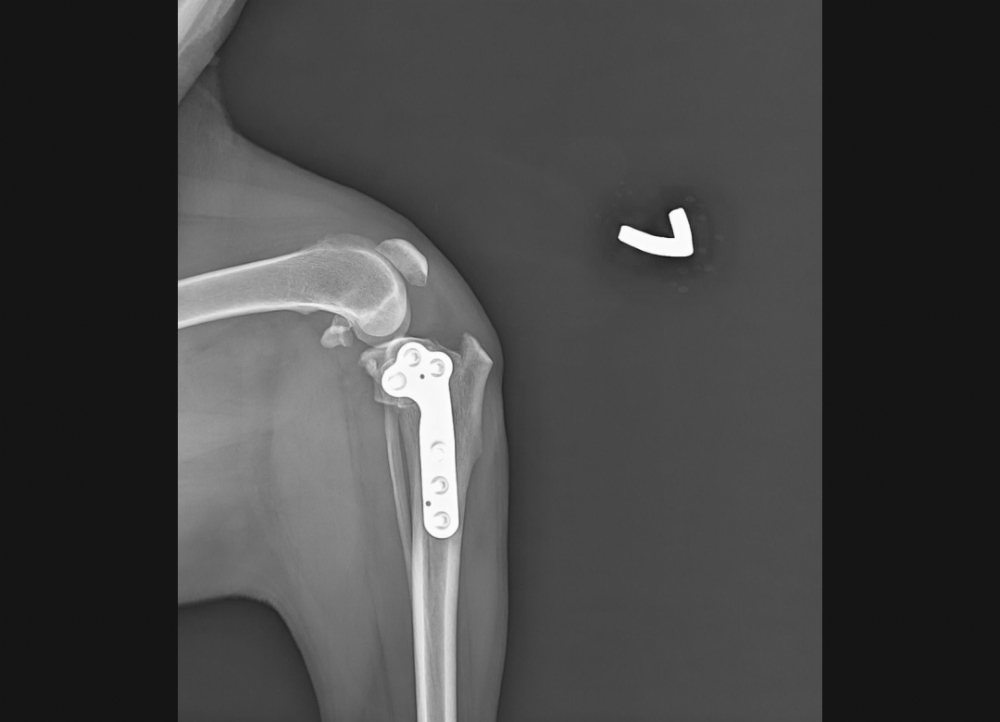

在脛骨進行環狀切割,藉由手術改變脛骨平台關節面的角度,並且使用TPLO骨板固定,使股骨不再向後滑動抑或是脛骨不再向前滑動,因此就不需額外使用線材做人工韌帶,也可避免人工韌帶可能發生的問題。

要施行TPLO前必須要嚴謹的評估手術必要性,並且需輕度麻醉/鎮靜拍攝X光才能精準計算所需改變的角度。

*本院引進義大利原廠Intrauma TPLO骨板器械來進行手術

理學檢查下抽屜試驗及脛骨施壓試驗發現異常懷疑十字韌帶有受損,和主人討論後續治療並且鎮靜拍x光評估脛骨平台水平矯形術(Tibial Plateau Leveling Osteotomy ; 簡稱TPLO)